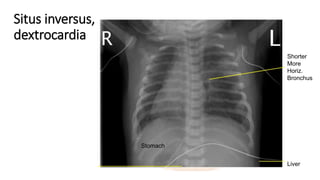

Situs inversus,

dextrocardia

Shorter

More

Horiz.

Bronchus

Liver

Stomach